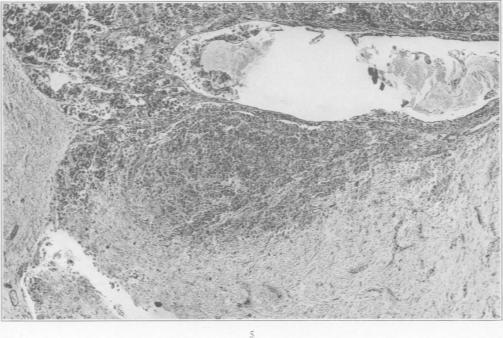

Hyperactivation of the Neurohypophysis as the Pathological Basis of Eclampsia and Other Hypertensive States.

Am J Pathol. 1934 Mar;10(2):145-176.31.

Hyperactivation of the Neurohypophysis as the Pathological Basis of Eclampsia and Other Hypertensive States.神经垂体的过度激活作为子痫及其他高血压状态的病理基础